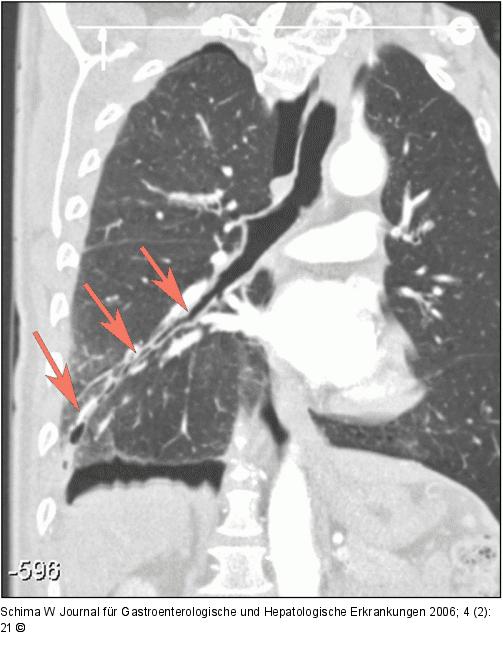

Abbildung 2b: Lungenparenchym Die 3D-Rekonstruktion der CT zeigt anschaulich den Trakt im Lungenparenchym vom Unterlappenbronchus bis zur Pleura (Pfeile). |

Die 3D-Rekonstruktion der CT zeigt anschaulich den Trakt im Lungenparenchym vom Unterlappenbronchus bis zur Pleura (Pfeile). |